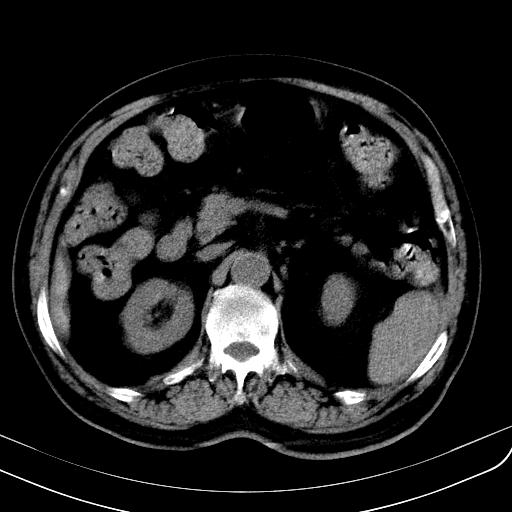

胃底靠近胃大弯处可见一圆形软组织影,直径为3.45cm,ct值约为30.1hu